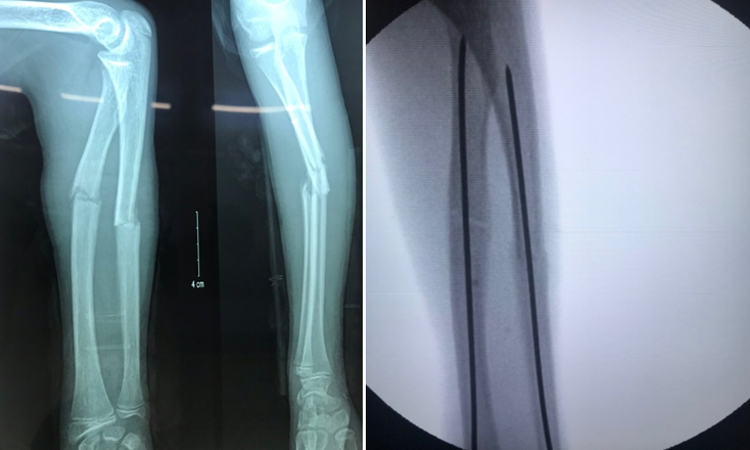

Gãy xương cẳng tay là tình trạng phần xương trụ và xương quay ở cẳng tay bị tổn thương sau các va chạm mạnh, chấn thương hay những tai nạn trong sinh hoạt.

Về việc điều trị tình trạng xương cẳng tay bị gãy thường sẽ đòi hỏi sự can thiệp từ các bác sĩ chuyên khoa bao gồm các cách thức thực hiện như bó bột, định hình hay phẫu thuật và chỉ định phụ thuộc vào tình trạng chấn thương của xương.